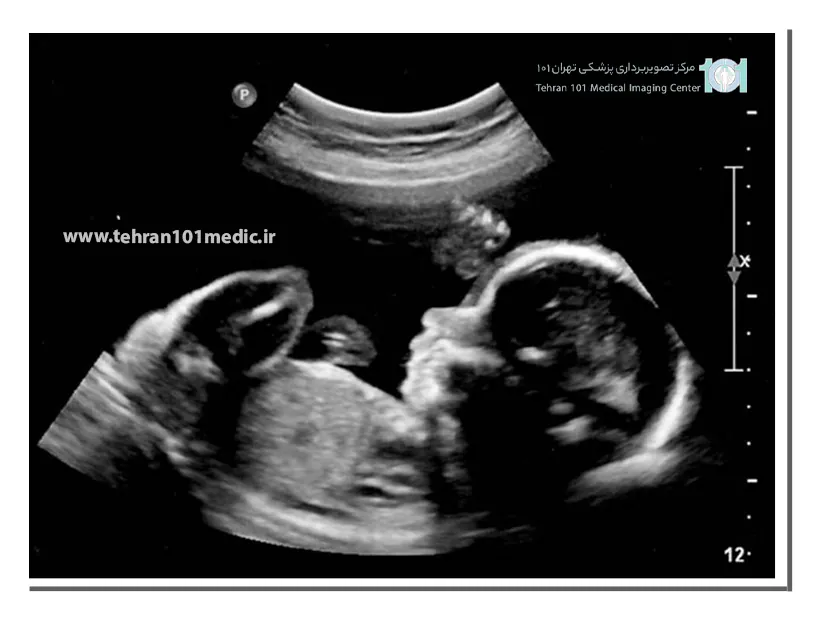

مشخصات جنین دختر در سونوگرافی

در تشخیص جنسیت جنین دختر پزشک به دنبال ویژگی های بارز آن که اندام تناسلی است می باشد.

مشخصات بارز اندام تناسلی جنین دخترعبارتند از:

علامت همبرگر:دراین علامت لابیا کلیتوریس به شکل یک همبرگر دیده می شود.

علامت ساژینال: در این مشخصه یک برجستگی تناسلی بین پاهای جنین مشاهده می شود که به آن nubگفته می شود.در صورتی که این برجستگی با زاویه کمتر از ۳۰درجه به سمت بالا باشد، احتمال دختر بودن جنین بیشتر است.